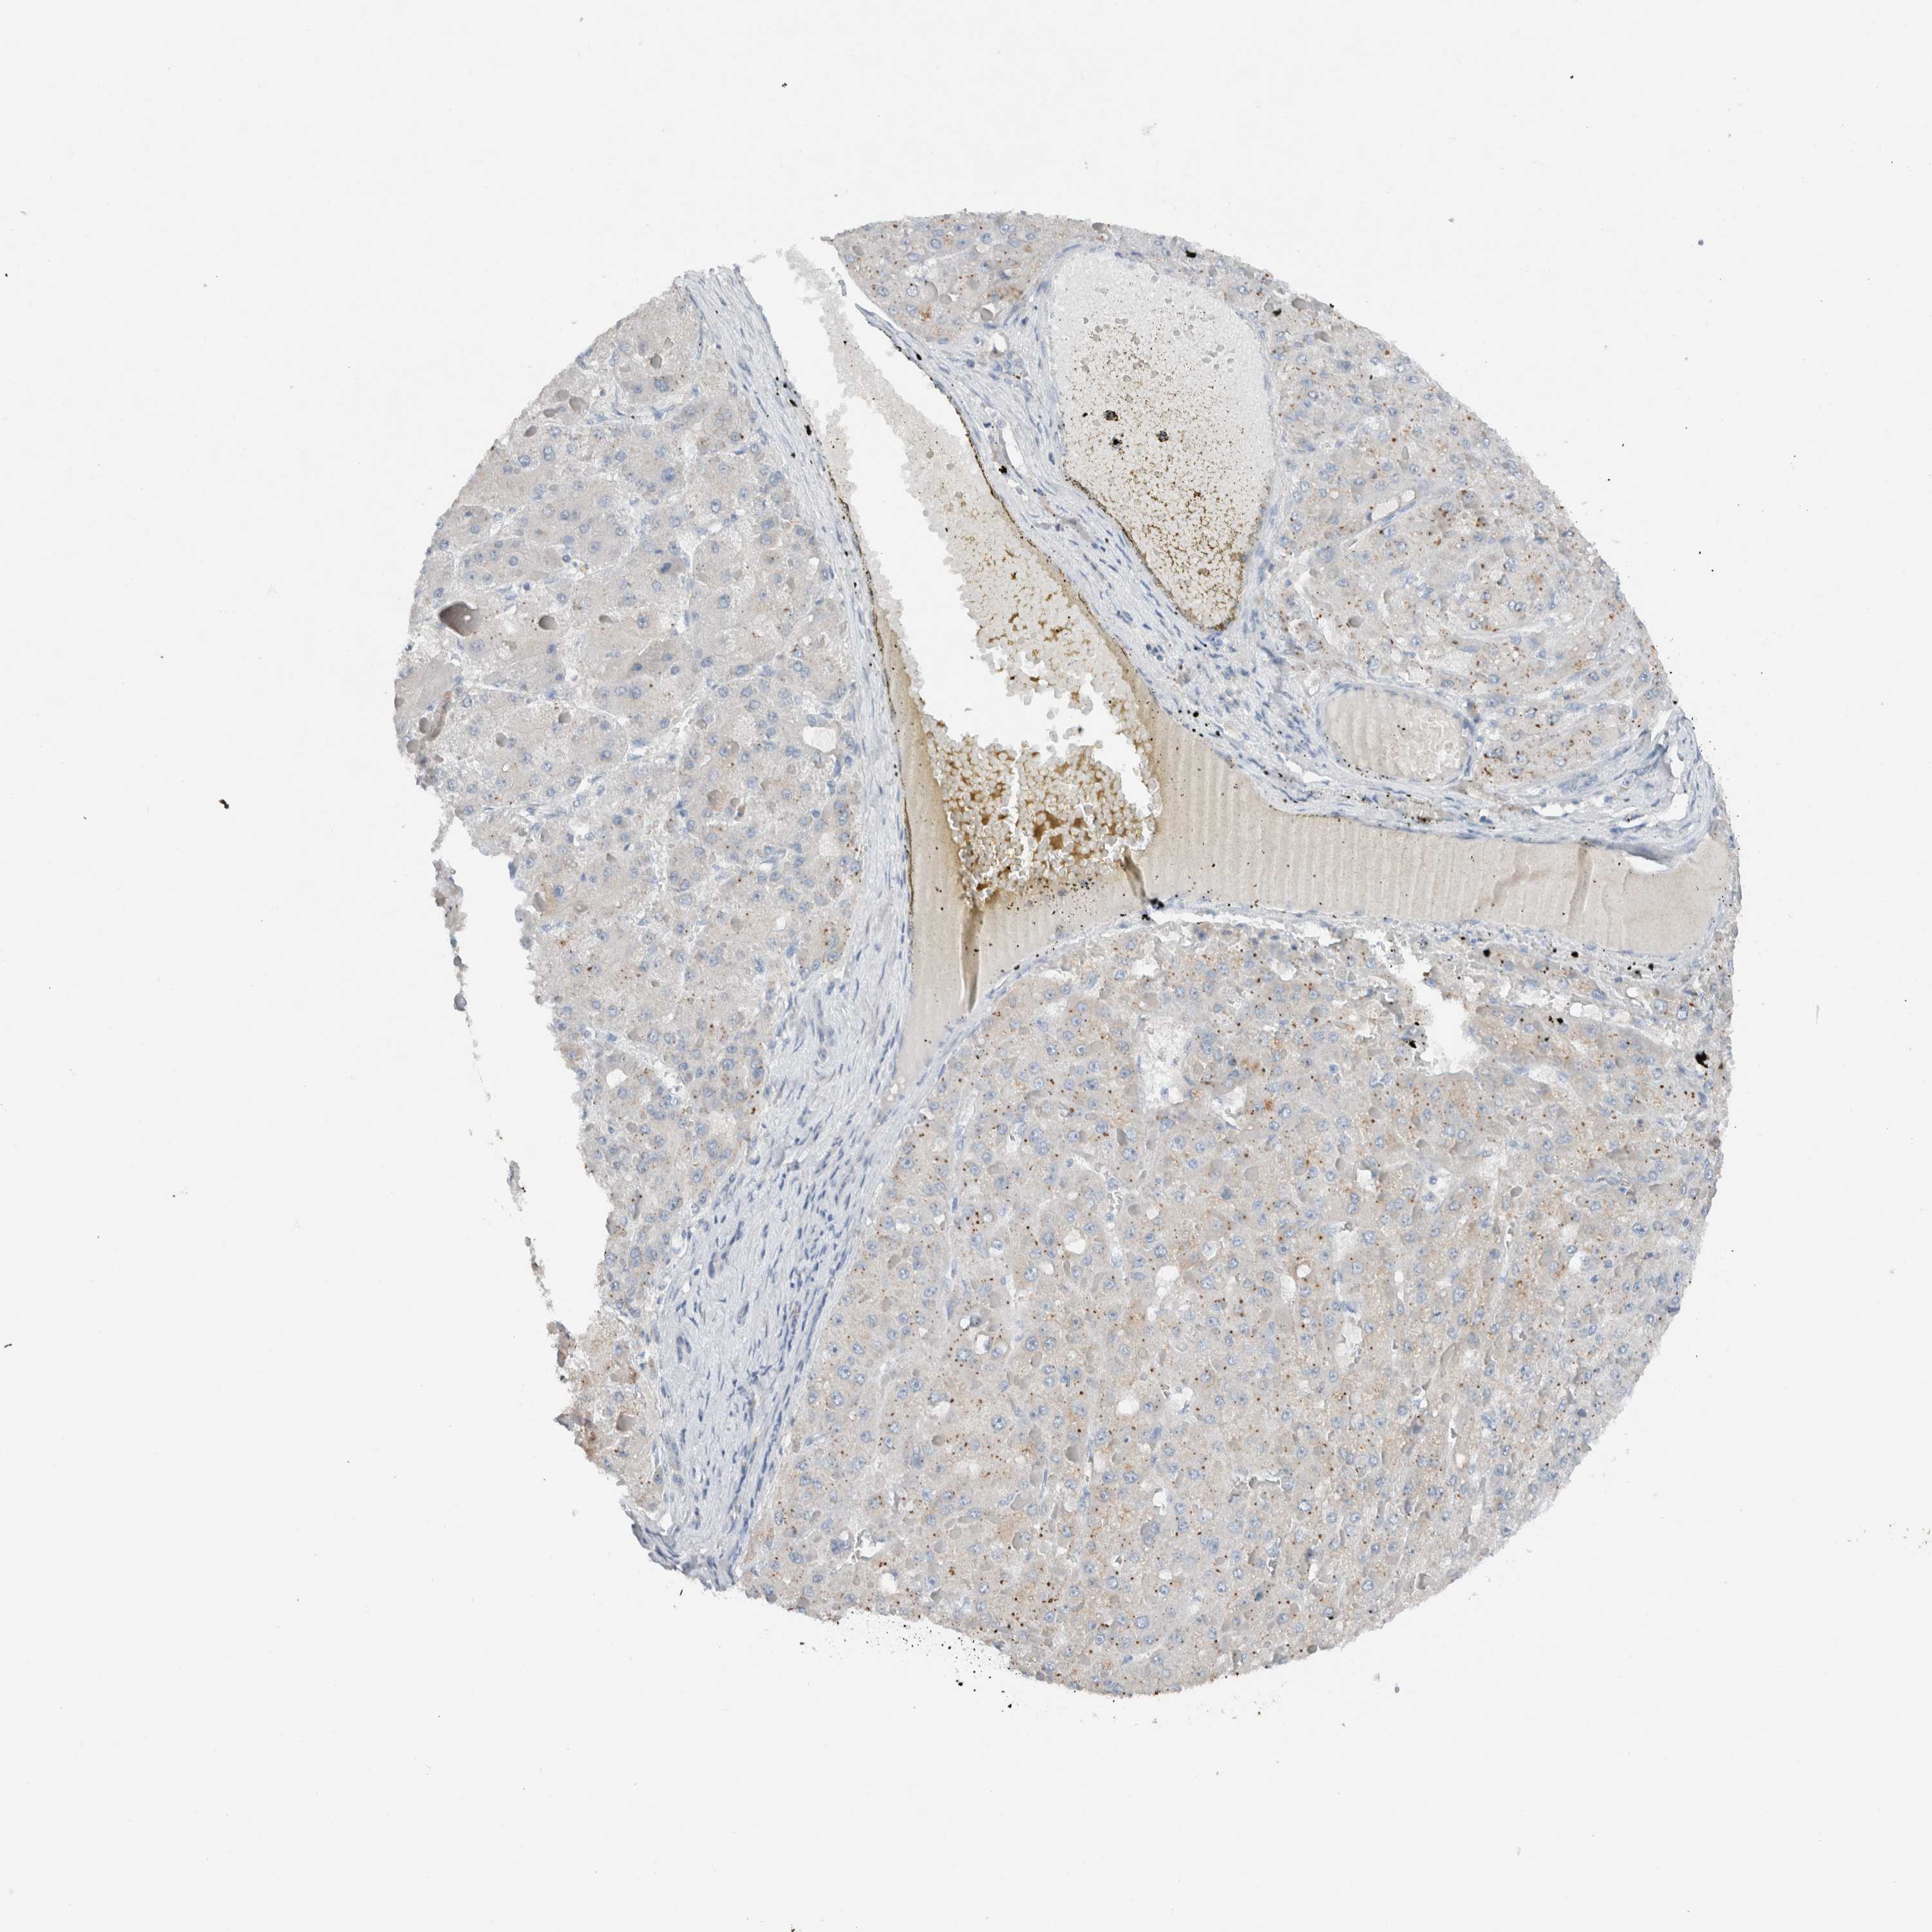

LIVER CANCER - Protein expressioni

A mouse-over function shows sample information and annotation data. Click on an image to view it in a full screen mode. Samples can be filtered based on level of antibody staining by selecting one or several of the following categories: high, medium, low and not detected. The assay and annotation is described here.

Note that samples used for immunohistochemistry by the Human Protein Atlas do not correspond to samples in the TCGA dataset.

Antibody stainingi

Antibody staining in the annotated cell types in the current human tissue is reported as not detected, low, medium, or high, based on conventional immunohistochemistry profiling in selected tissues. This score is based on the combination of the staining intensity and fraction of stained cells.

Each image is clickable and will lead to virtual microscopy that enables deeper exploration of all samples and also displays staining intensity scores, fraction scores and subcellular localization as well as patient and tissue information for each sample.

Antibody HPA023544

Staining

High

Medium

Low

Not detected

Intensity

Strong

Moderate

Weak

Negative

Quantity

>75%

75%-25%

<25%

None

Location

Nuclear

Cytoplasmic/membranous

Cytoplasmic/membranous,nuclear

Cholangiocarcinoma

Carcinoma, Hepatocellular, NOS